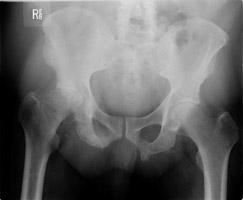

- Click on the image for a larger versionCAP radiograph of the pelvis. This is a different patient with prostate cancer. There are multiple sclerotic metastases.

- Click on the image for a larger versionDAP radiograph of the left hip. Two years later, the patient presents with hip pain and a femoral neck fracture (basicervical).